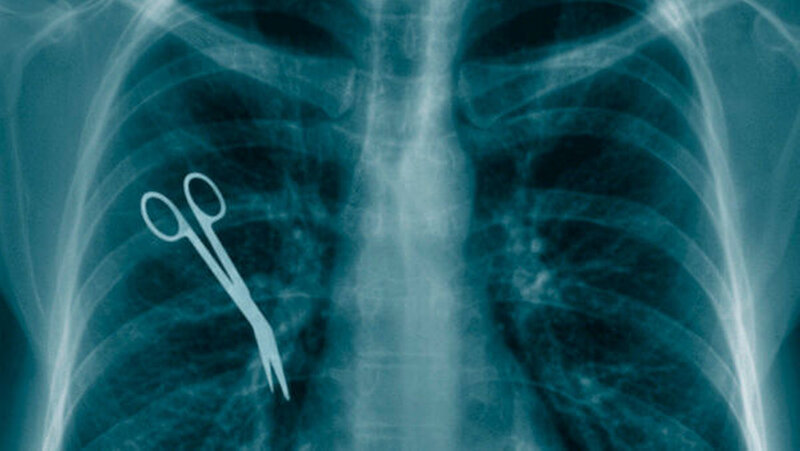

Größere Angst vor Fehlern

Die Zahl der nachgewiesenen Behandlungsfehler sowohl in den Arztpraxen als auch in Krankenhäusern hat sich auch 2012 im Promillebereich bewegt. In 1.889 Fällen machten die Gutachter und Schlichter der Ärztekammern Behandlungsfehler als Ursachen von Schädigungen der Patienten aus, gab die Bundesärztekammer (BÄK) am Montag bekannt.

In weiteren 391 Fällen wurden Fehler aufgedeckt, die nicht im Zusammenhang mit der vom Patienten monierten Behandlung standen. 82 Menschen starben aufgrund von Behandlungsfehlern in Kliniken - weil dort, so die Aussage, die schwereren Fälle behandelt werden. In 72 Prozent betrafen die überprüften Fälle die Kliniken, nur in 28 Prozent die Praxen.